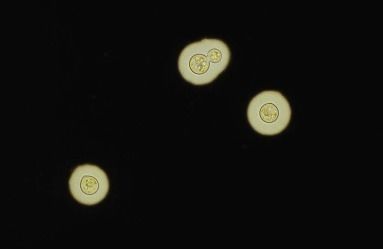

Malassezia Leveduriforme Blastoconídeos com colarete |